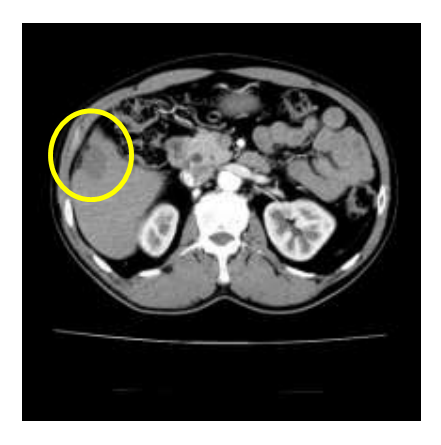

Chụp CT ổ bụng: Hình ảnh khối giảm tỉ trọng gan hạ phân thùy V kích thước 25×30 mm, không ngấm thuốc sau tiêm.

Hình 2: Hình ảnh chụp cắt lớp vi tính ổ bụng không thấy tổn thương di căn gan (vòng tròn vàng).